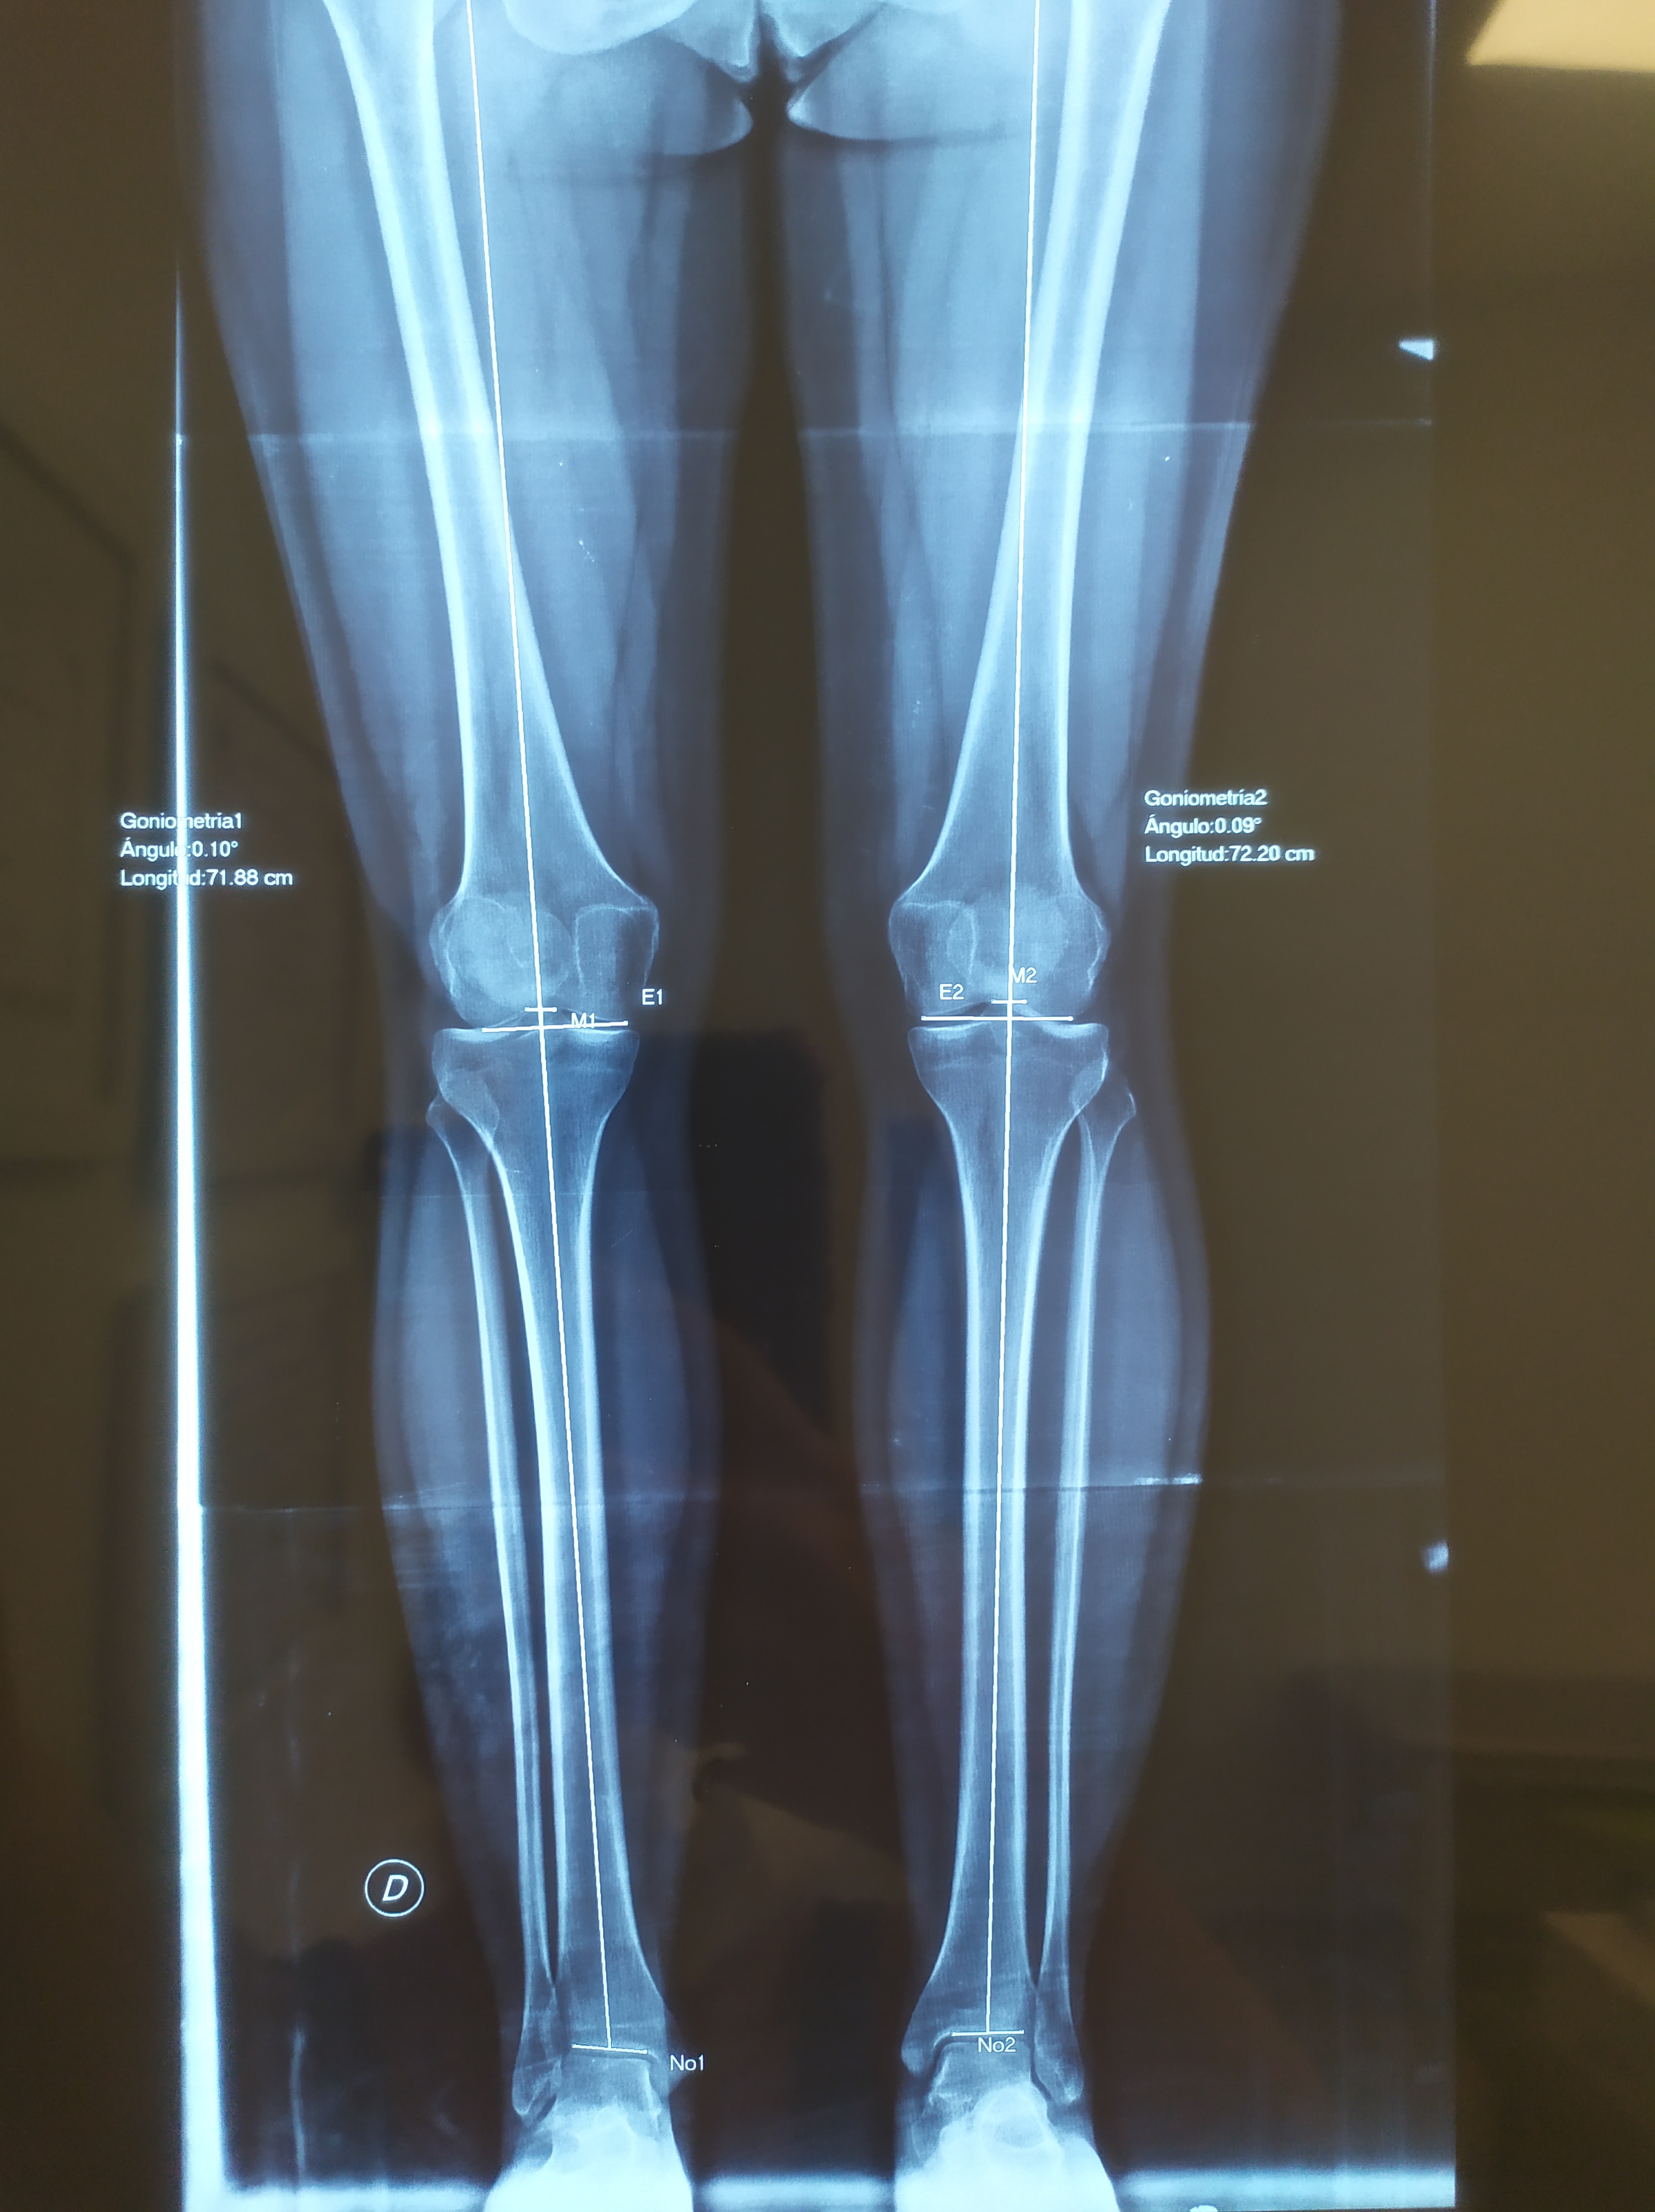

Decidieron hacerme una radiografía de medición de miembros y efectivamente, salía lo que pensábamos todos. Tengo una pierna un poco más larga que la otra. No es algo que se note a leguas, pero sí algo que me ha provocado un pinzamiento en la L4 y L5 y probablemente por lo que la primera operada, que es la pierna más corta, me duela.

Voy a dejaros por aquí las imágenes de la Rx.